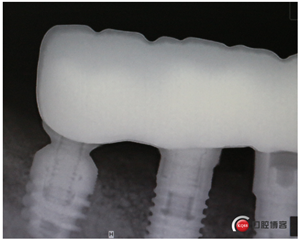

試戴冠,看起來(lái)還不錯(cuò)哈,但我不滿意,大家看看有什么問(wèn)題?看看下頜那幾顆比較明顯。

再看看片子。

問(wèn)題在這里,不給留位置怎么會(huì)有齦乳頭,沒(méi)有間隙怎么清潔?這完全是技工的錯(cuò)吧?算了我自己修整一下吧。

再看看是不是效果好多了?哼!我就是個(gè)較真兒的人。